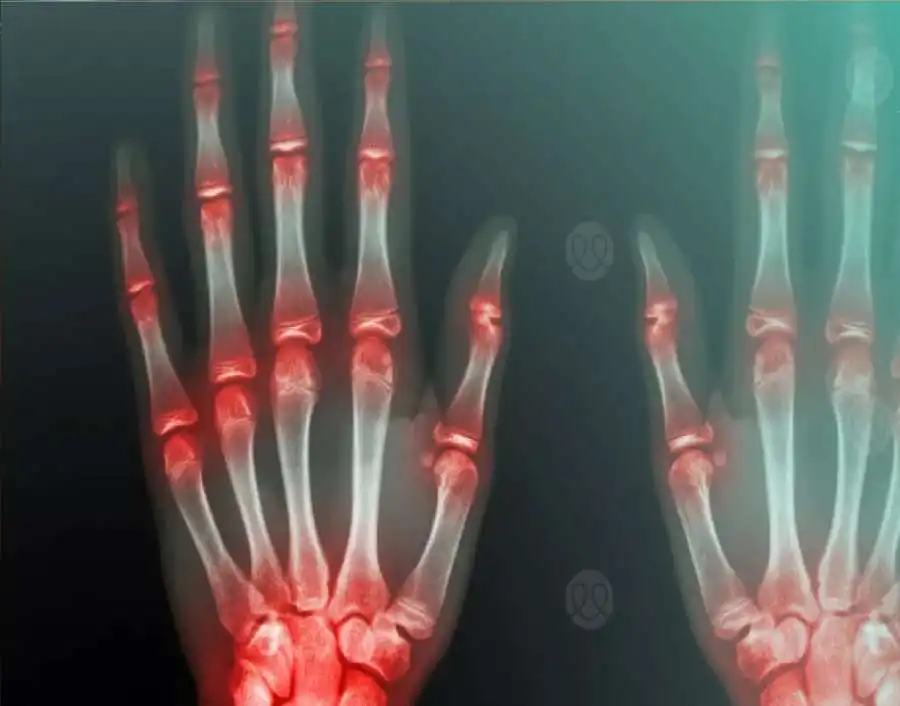

مدار الساعة - طوّر باحثون برنامجاً رياضياً مبتكراً قادراً على تقليل آلام التهاب المفاصل الروماتويدي بشكل ملحوظ، خلال أقل من ثمانية أسابيع فقط، مما قد يمثل نقلة نوعية في أساليب العلاج المكمّلة لهذا المرض المزمن.

وأظهر البرنامج، الذي صُمّم خصيصاً لمرضى التهاب المفاصل الروماتويدي، وهو اضطراب مناعي ذاتي يؤدي إلى مهاجمة الجسم لنسيج المفاصل السليم، نتائج واعدة بعد تطبيقه مرتين أسبوعياً لمدة ساعة في كل جلسة.

يُذكر أن التهاب المفاصل الروماتويدي يُصيب أكثر من 1.3 مليون شخص في المملكة المتحدة وحدها، وهو مرض مزمن لا علاج نهائي له، إلا أن العديد من الأدوية مثل البيولوجيات ومن أبرزها دواء "أداليموماب"، تُستخدم لتقليل الاستجابة المناعية والحد من تدهور المفاصل.